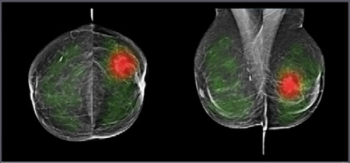

Adjunctive use of an artificial intelligence (AI) software demonstrated nearly equivalent sensitivity and over 28 percent higher accuracy in comparison to radiologist assessment of breast ultrasound images for breast lesions, according to new research presented at the recent Society of Breast Imaging (SBI) conference.

Emerging breast ultrasound research showed the use of computer-aided diagnosis (CAD), powered by deep learning, led to 24 percent and 36.9 percent improvements in accuracy and specificity, respectively, in the use of BI-RADS classifications by radiologists without breast ultrasound expertise.